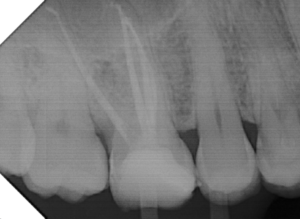

Alguns trabalhos